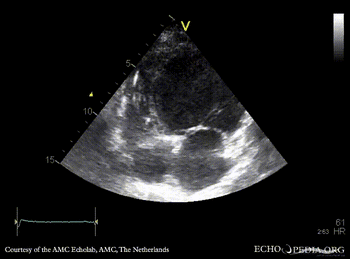

E00705.gif E00706.gif

PLAX: dilated left ventricle, reduced systolic function PSAX